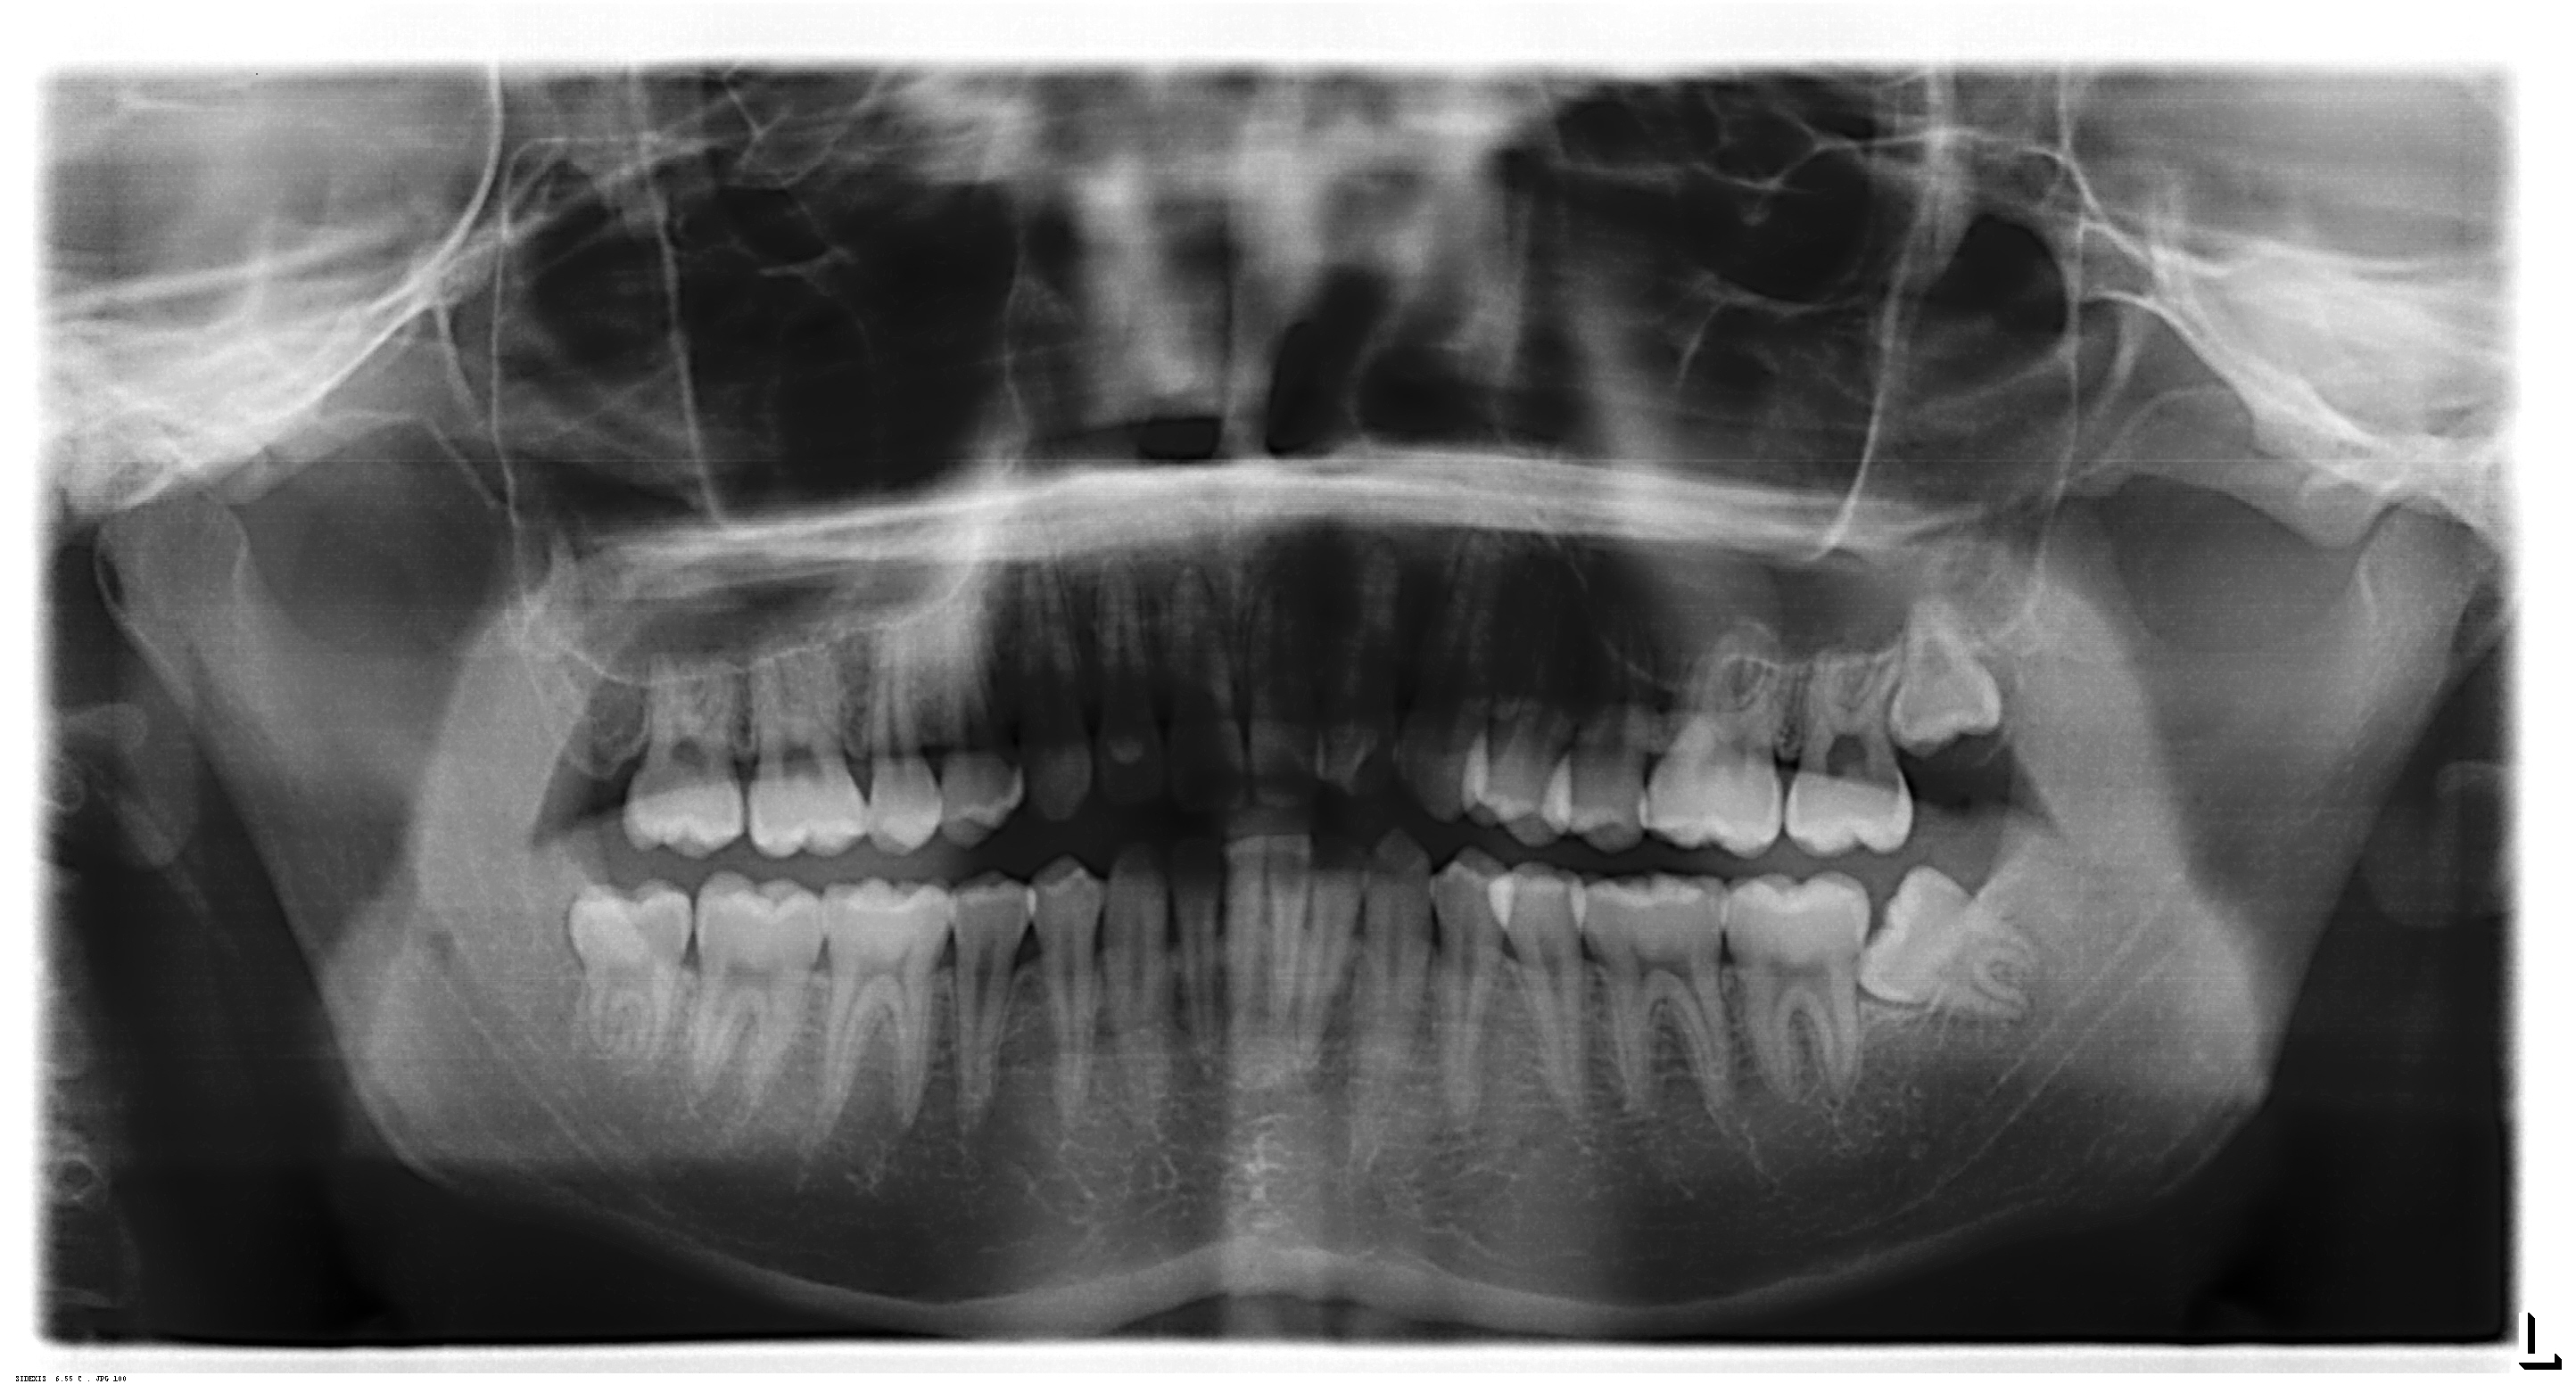

(»çÁø - 3)

±×¸®°í »ç¶û´Ï°¡ À߸ø ³ª¼ ¾ÕÀÇ ¾î±Ý´Ï µÞ¸é¿¡ Ä¡¾Æ¿ì½ÄÁõ(»çÁø 3)ÀÌ »ý±â°Å³ª ±â¿ï¾îÁø »ç¶û´Ï ¶§¹®¿¡ Ä¡¼®ÀÌ ½±°Ô »ý°Ü¼ ÁÖº¯ÀÇ ÀÕ¸ö¿¡ Ä¡ÁÖÁúȯÀÌ »ý±â´Â °æ¿ì°¡ ÀÖÀ» ¼ö ÀÖ½À´Ï´Ù.